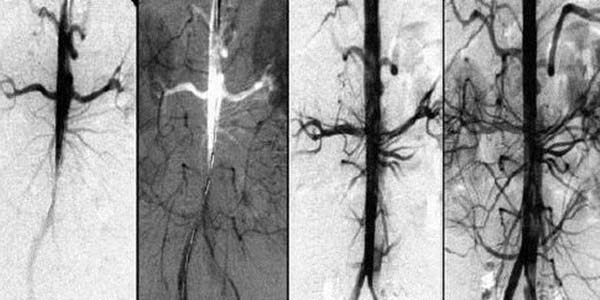

- Complicaciones tromboembólicas venosas. Cuando se forman coágulos de sangre en las venas, que pueden ingresar a un órgano en particular, lo que interrumpe el flujo sanguíneo y puede causar un resultado trágico.

El tratamiento de los trastornos circulatorios en los vasos es limpiar el cuerpo de las impurezas acumuladas y restaurar el proceso normal de la circulación sanguínea.

La restauración de la circulación sanguínea normal es un proceso complejo que depende del estado de todos los vasos en el cuerpo. Ponerlos en orden puede mejorar la calidad de vida de muchas personas.

Si los vasos sanguíneos del corazón (arterias coronarias) están obstruidos con depósitos de

colesterol, esto inicialmente causa angina, pero luego puede provocar un infarto de

miocardio. Y los vasos perdidos que no entregan la cantidad correcta de sangre al cerebro

son el camino directo para un derrame cerebral.

2. Mejora la circulación sanguínea

Reduce el riesgo de coagulación de la sangre y tiene un efecto antioxidante.

3. Aumenta la resistencia y elasticidad de las paredes de los vasos

Esto previene la formación de placa y reduce el riesgo de accidente cerebrovascular en un

factor de 11.